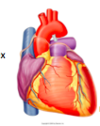

Describe the hearts shape from the anterior view

Apex of the heart hangs the most inferior and to the left, running laterally to the right is the diaphragmatic surface. The appendage (purple) is the right atrium.

Describe the shape of the heart from the posterior view

The base of the heart can be seen from the posterior view and is formed by the meft atrium NOT the diaphragmatic surface.

Below the base of the heart is the diaphragmatic surface formed by the let ventricle.

(can also see the R and L pulmonary arteries, SVC and IVC entering the Right atrium and the arch of the aorta.

The heart is a _________ structure that rotates to the _____ during development.

The heart is a midline structure that rotates to the left during development.